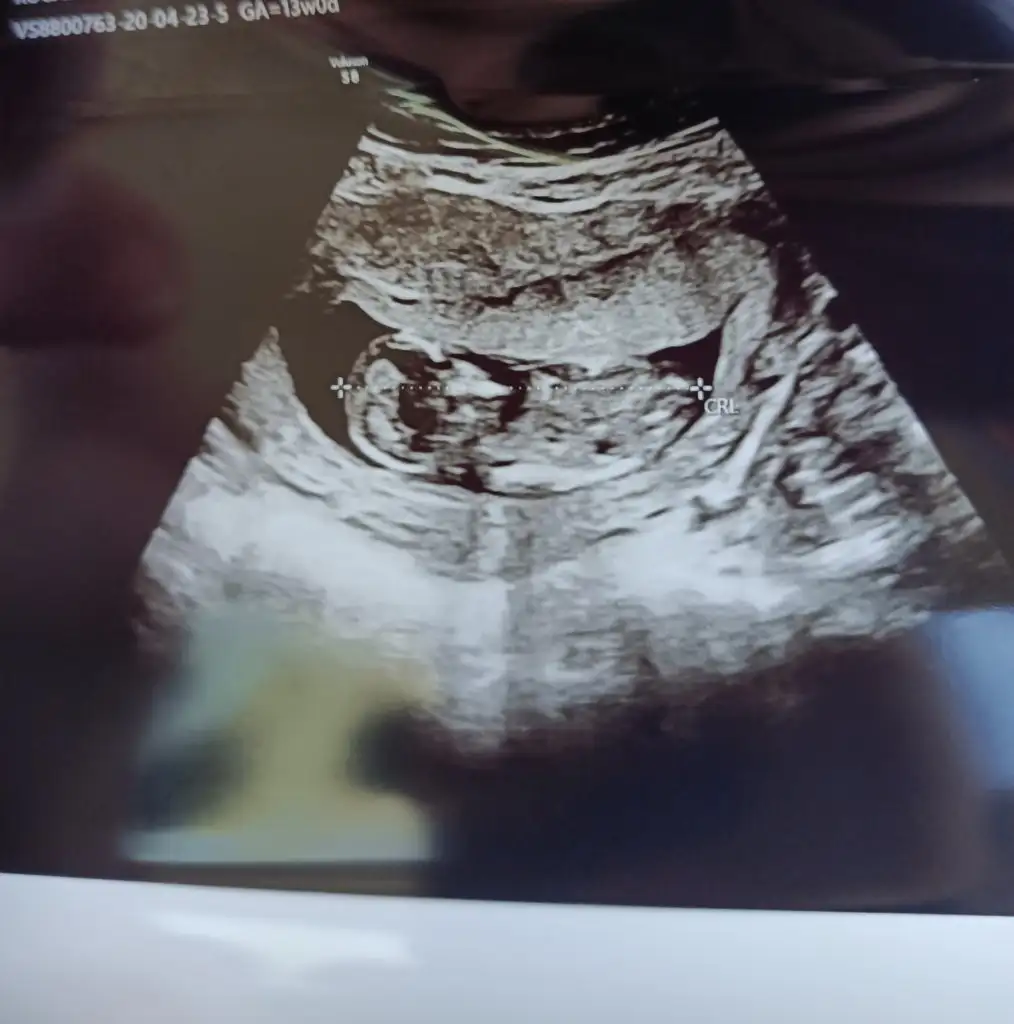

Merhabalar anlayanlar benim görüntülerede bakabilirmi 13 haftalık olduk merak ediyorum 😉

• IMG20200423112010.webp

IMG20200423112010.webp

25,9 KB · Görüntüleme: 54